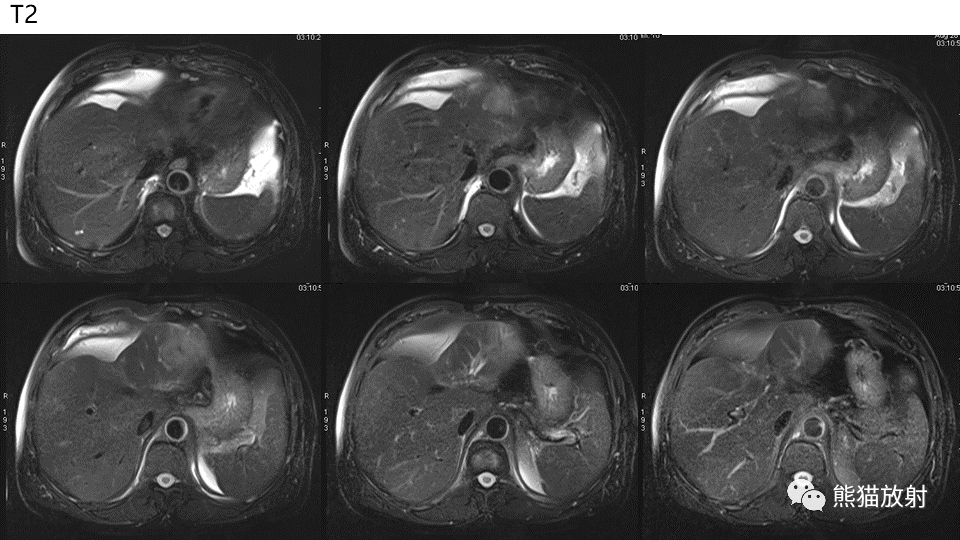

【PPT】肝内胆管细胞癌 VS 肝脓肿